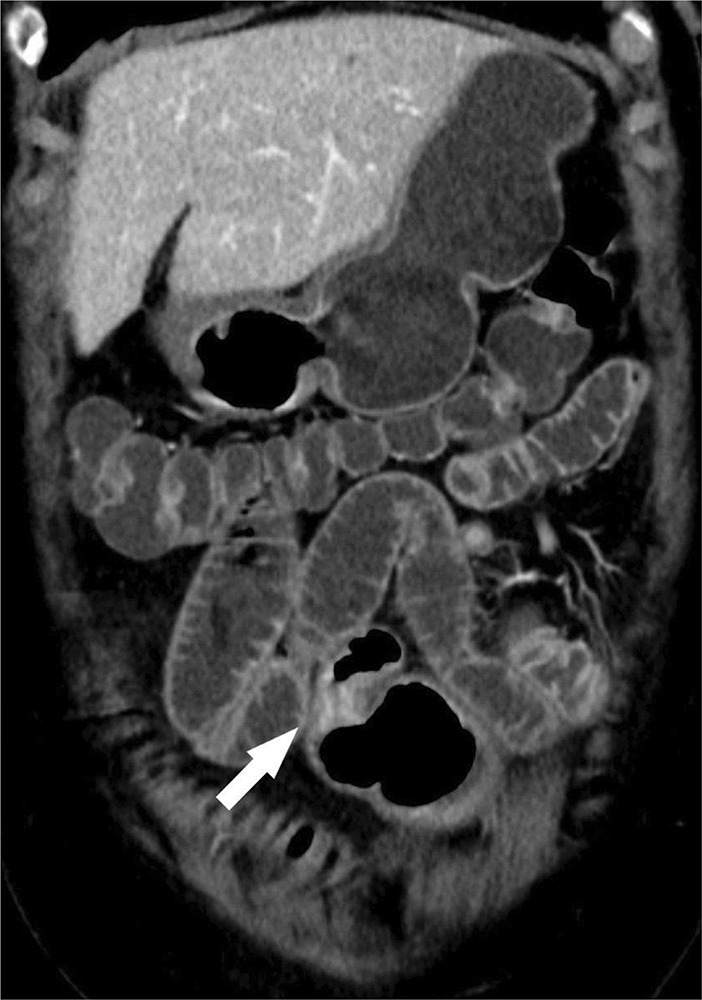

教学点:CT小肠造影/小肠灌肠术可充分评估小肠神经内分泌肿瘤及肠外异常。

Teaching point: CT enterography/enteroclysis allows adequate evaluation of neuroendocrine small bowel tumor and extra-enteric abnormalities.